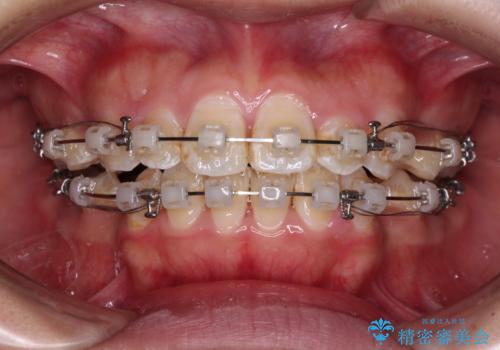

- クリアブラケット

- 2年2ヶ月

- 前歯のクロスバイトと、口元が閉じにくいとのことで来院された患者様です。

口元の突出感を改善する必要があるため、上下左右の第1小臼歯4本を抜歯し、ワイヤー装置にて矯正治療を行うこととしました。

むし歯のリスクが高かったため、治療が長期化しないように心がけました。

当初の予定通り、2年強で無事に治療を終えることができました。